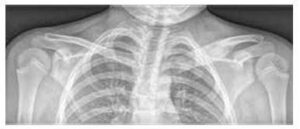

Слика бр. 1

Палмоплантарна пустулоза код пацијента са КРМО

Значајно увећање и остеолитичке лезије медијалног краја леве клувикуле и едем меких ткива на рентгенском снимку